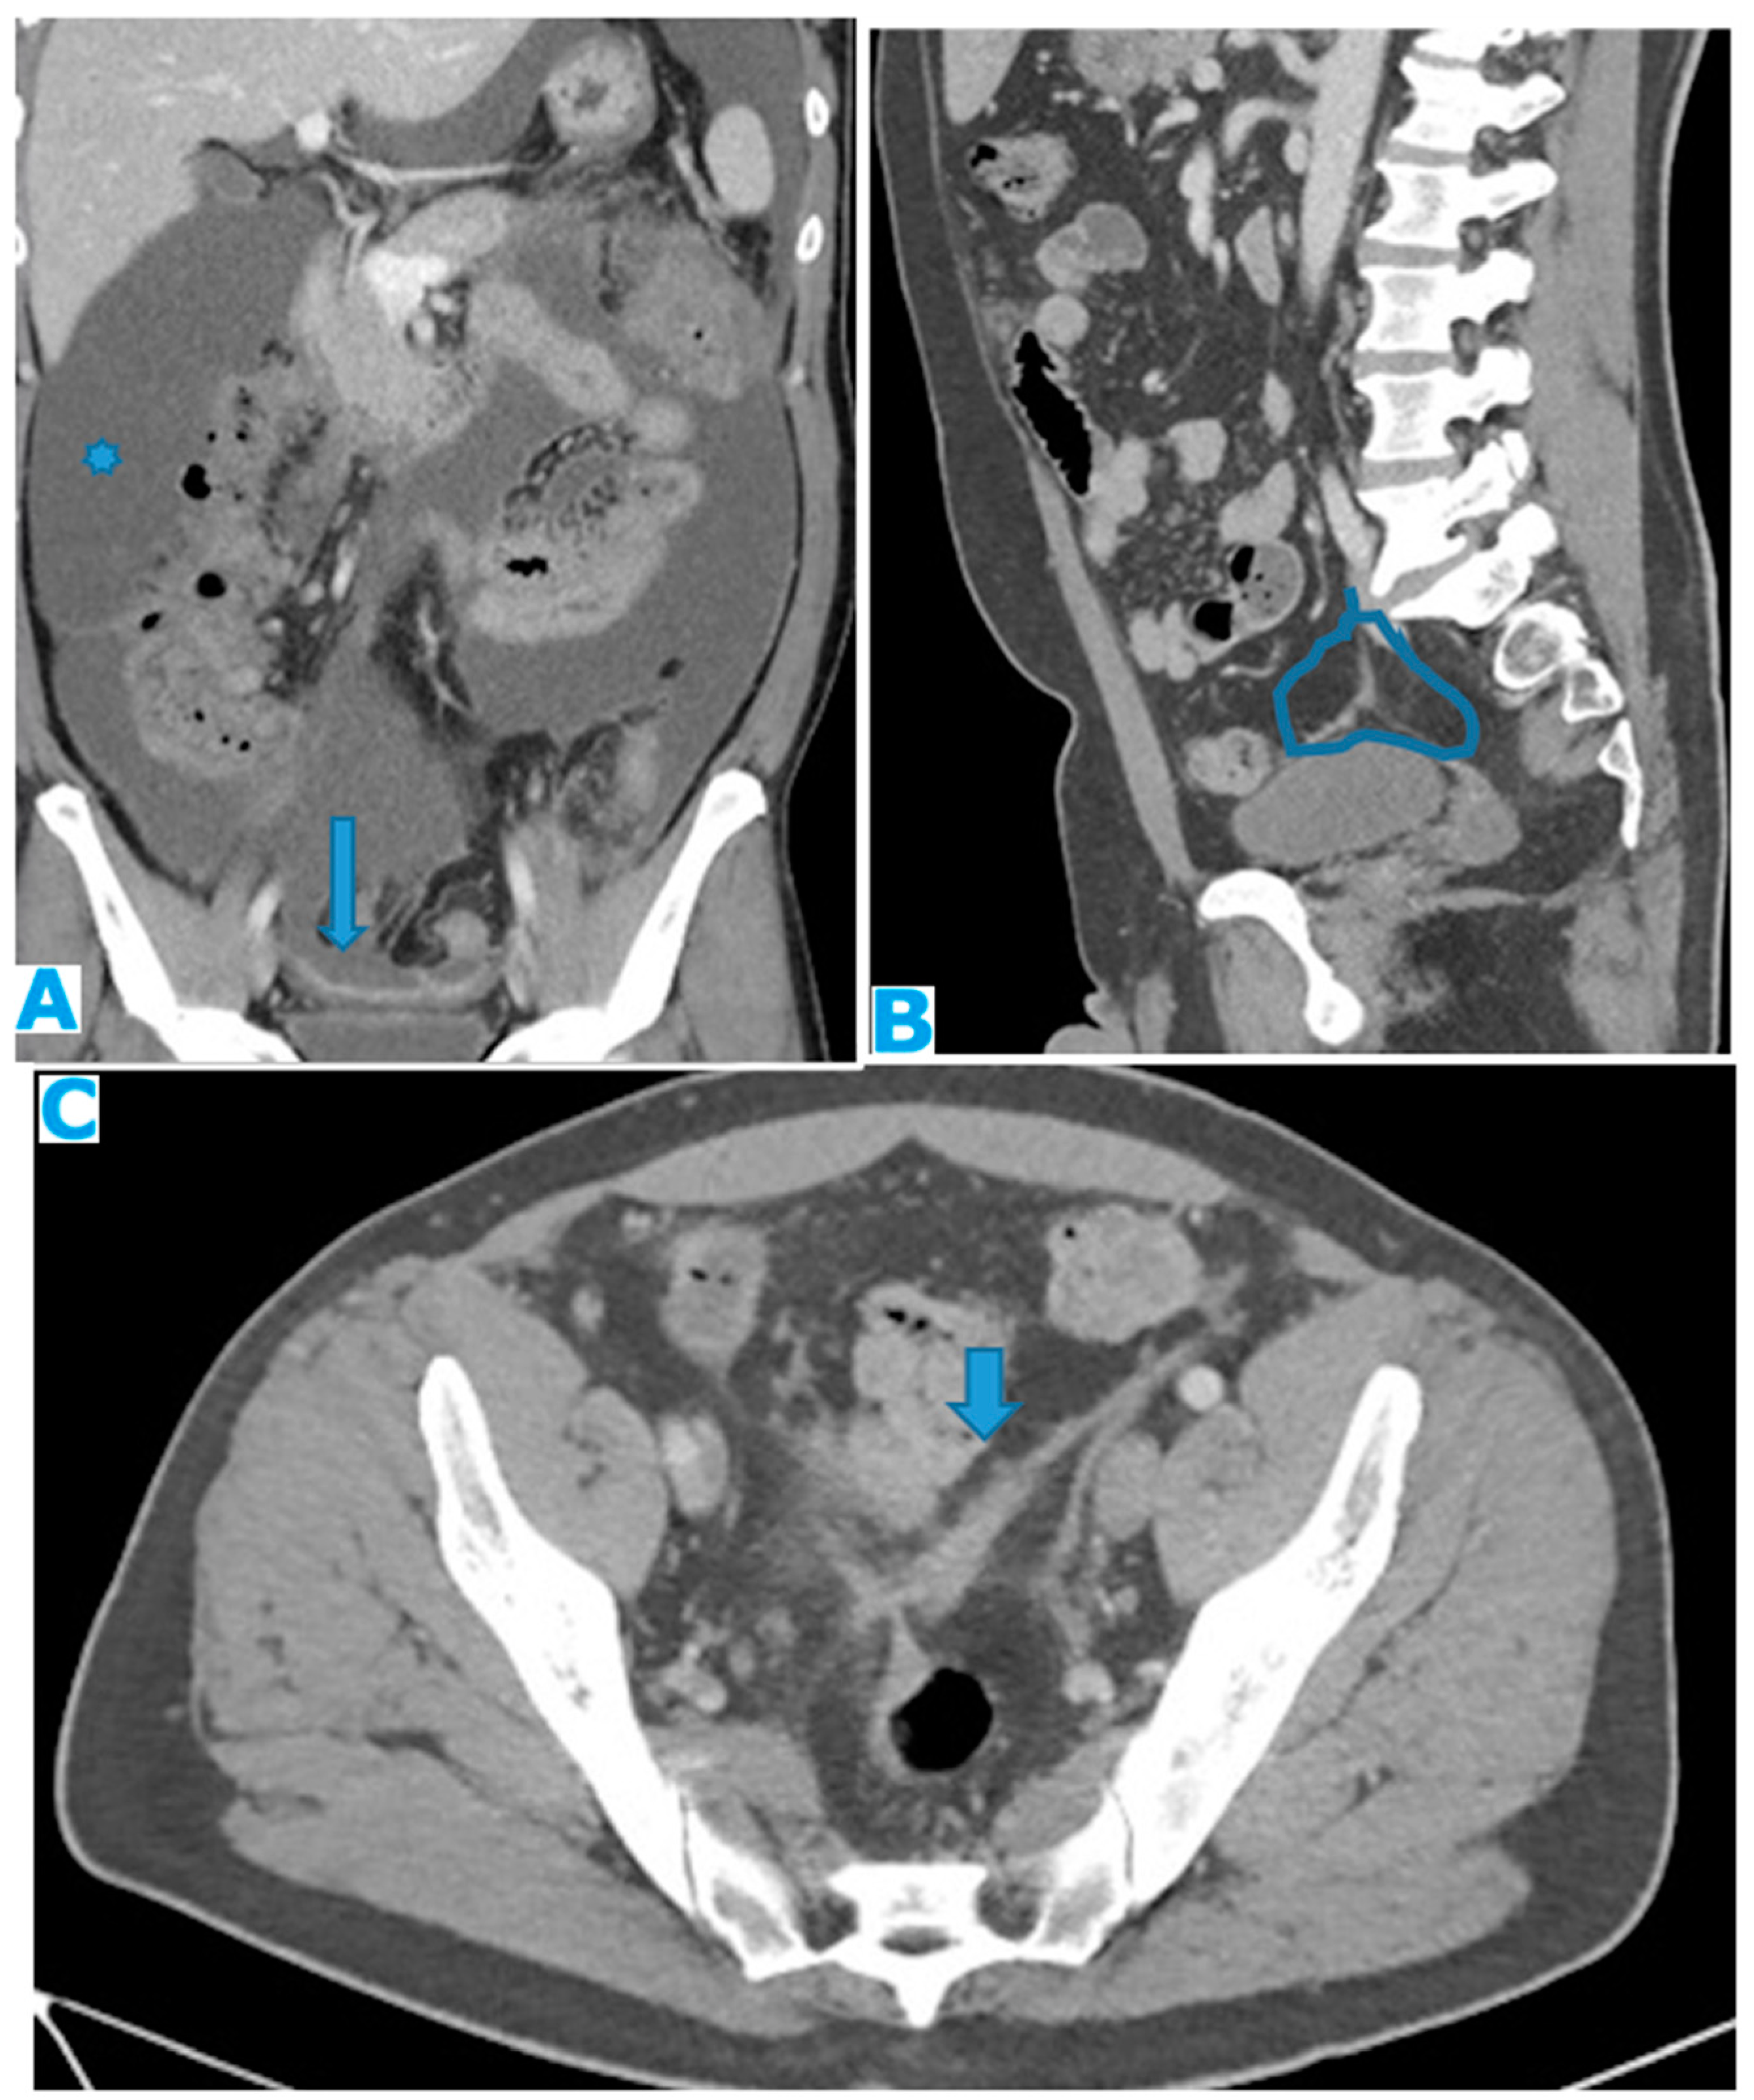

Figure 32.

CE-CT Coronal MPR (A). PC from colon carcinoma: Observe how the parietal peritoneum does not reach the pelvis floor. Ascites (*). Deposits within the pelvic reflexion (arrow). Sagittal MPR (B), axial CE-CT (C). PC from adenocarcinoma of the appendix: Irregularly thickened peritoneal reflexion due to seeding. Observe on the sagittal MPR how the peritoneal reflexion covers the dome of the urinary bladder and then descends, following its posterior wall.